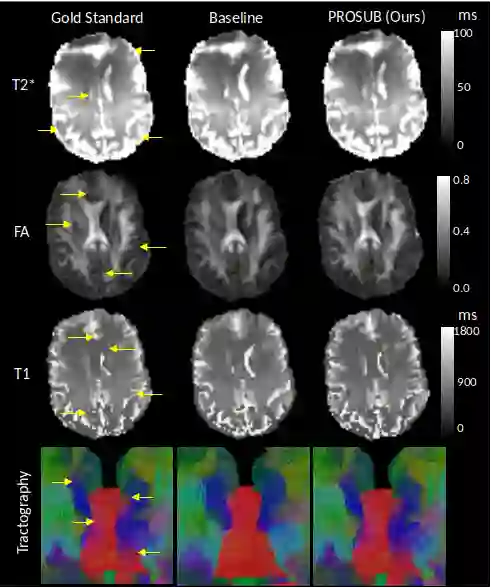

We present PROSUB: PROgressive SUBsampling, a deep learning based, automated methodology that subsamples an oversampled data set (e.g. multi-channeled 3D images) with minimal loss of information. We build upon a recent dual-network approach that won the MICCAI MUlti-DIffusion (MUDI) quantitative MRI measurement sampling-reconstruction challenge, but suffers from deep learning training instability, by subsampling with a hard decision boundary. PROSUB uses the paradigm of recursive feature elimination (RFE) and progressively subsamples measurements during deep learning training, improving optimization stability. PROSUB also integrates a neural architecture search (NAS) paradigm, allowing the network architecture hyperparameters to respond to the subsampling process. We show PROSUB outperforms the winner of the MUDI MICCAI challenge, producing large improvements >18% MSE on the MUDI challenge sub-tasks and qualitative improvements on downstream processes useful for clinical applications. We also show the benefits of incorporating NAS and analyze the effect of PROSUB's components. As our method generalizes to other problems beyond MRI measurement selection-reconstruction, our code is https://github.com/sbb-gh/PROSUB